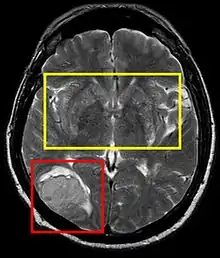

Stroke brain (similar to cerebral softening) | |

Cerebral softening, also known as encephalomalacia, is a localized softening of the substance of the brain, due to bleeding or inflammation. Three varieties, distinguished by their color and representing different stages of the disease progress, are known respectively as red, yellow, and white softening.[1][2]